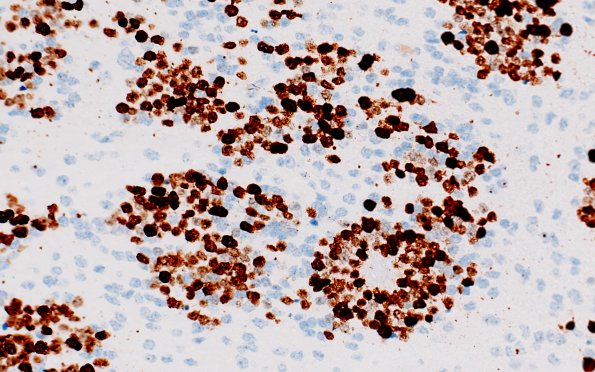

ETMR - Embryonal Tumor Multilayered Rosettes

Not surprisingly the embryonal rosettes show strong Ki67 immunoreactivity. (Ki67 IHC)